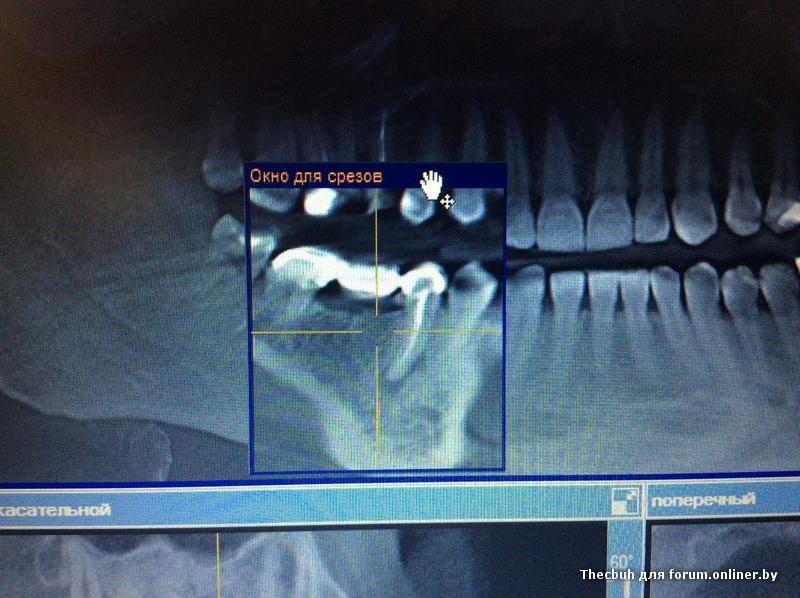

Во всех депульпированых зубах есть проблемы, плюс в пазухе слева от 25 зуба есть нюанс

inycik:Во всех депульпированых зубах есть проблемы, плюс в пазухе слева от 25 зуба есть нюанс

16,15 на удаление, потом синус и имплантация

Все зубы перелечила. это кт до лечения. Сейчас под временными коронками. Предлагают имплантацию 1.5,2.5 и 4.5 (убрать мост, т.к. 4.6 сильно разрушен). 1.5 удалить и сразу же имплант, но про наращивание не говорили.

А скажите, что в пазухе? Это как-то повлияет на имплантацию